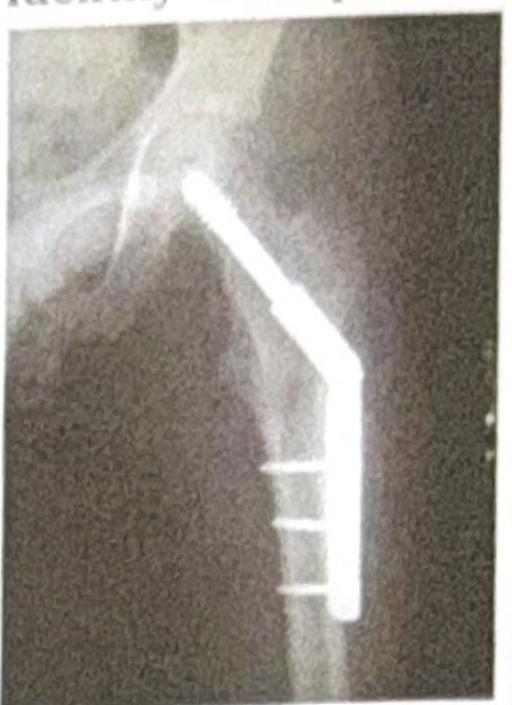

Identify the implant shown in the image:

Explanation: ***Dynamic hip screw*** - The image shows a **lag screw** inserted into the femoral neck and head, which slides within a **side plate** attached to the femoral shaft with cortical screws. - This construct allows for controlled **dynamic collapse** and impaction at the fracture site, promoting healing and providing stable fixation for **extracapsular hip fractures**. *Cannulated hip screw* - Cannulated screws are typically used in a **parallel configuration** or as a single large screw for hip fractures, particularly **femoral neck fractures**. - They do not feature a **side plate** that extends down the femoral shaft for additional fixation. *Condylar hip screw* - A condylar hip screw (DCS) is used for **distal femur fractures**, often extending into the **condyles**. - It involves a different angulation and design compared to the proximal femoral implant seen, which is fixed to the femoral shaft. *Intramedullary nail* - An intramedullary nail is inserted into the **medullary canal** of the bone, running through its center. - While some hip nails (e.g., trochanteric nails) have a cephalic screw component, they primarily stabilize the shaft from within, unlike the **extracortical side plate** seen here.